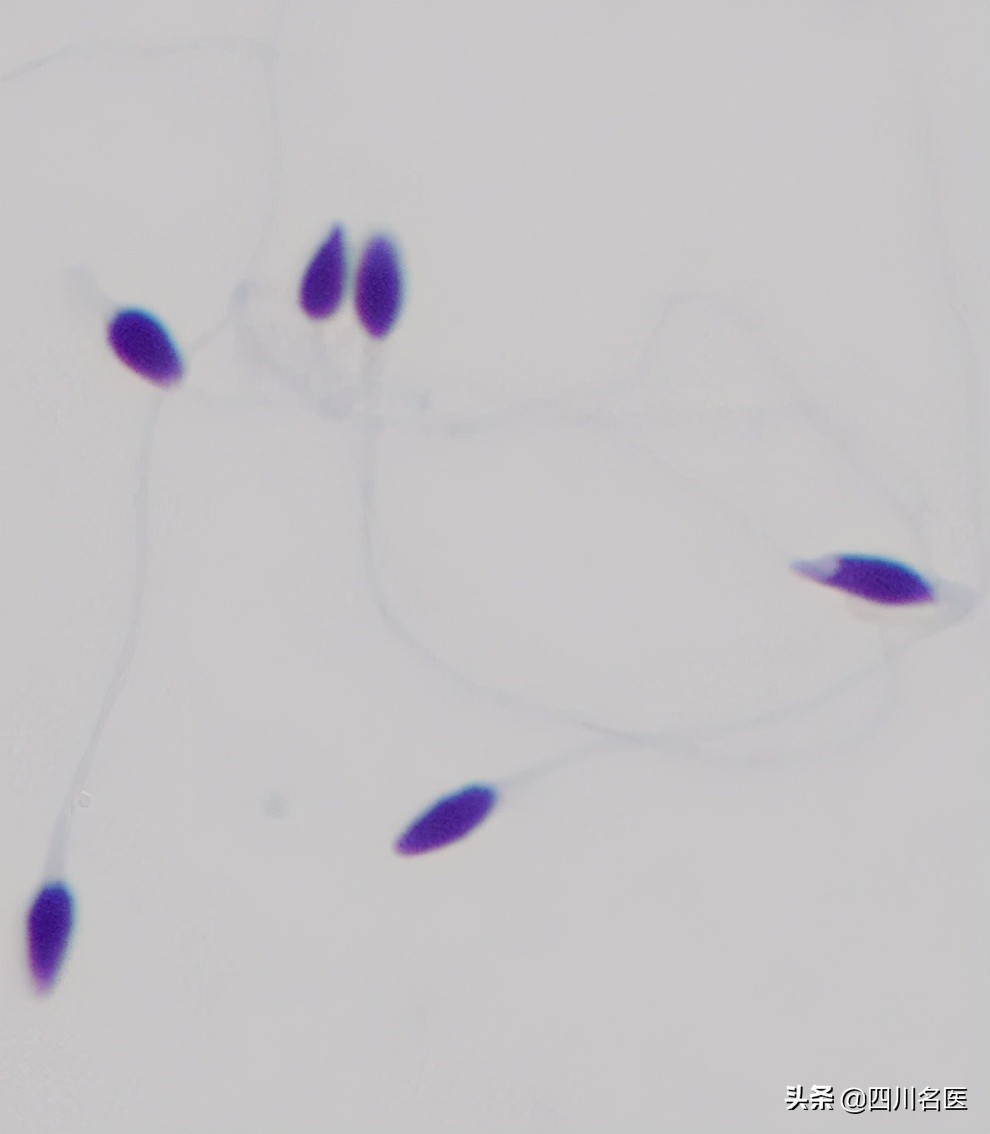

▲多头多尾精子

▲锥形头精子

▲梨形头精子

▲精子中的“大脖子病” and “歪脖子病”